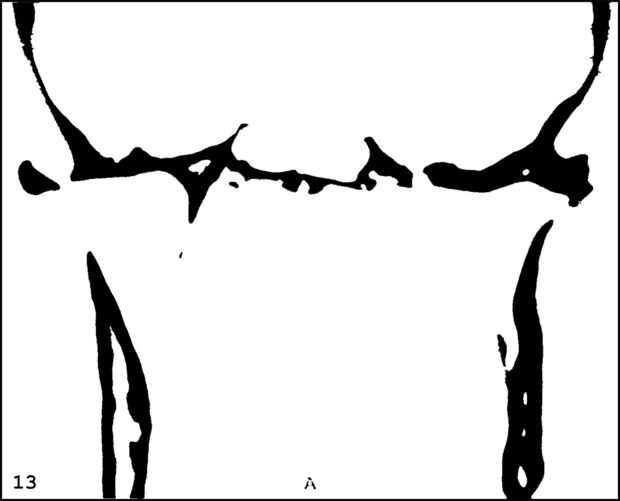

¡ Wow! Este fue por menos de 12 horas y tengo 1.000 visitas! Esto es sólo mi segundo instructable, así que estoy encantada. Decidí seguir adelante y publicar las imágenes que utiliza. Se trata de MRI de mi esposa, así que ella sólo puede tener lo mundos primer código abierto jefe. Mi lámpara utiliza solamente las primeras 16 capas, pero te di todos 34 que representa. Seguir adelante y usar estas imágenes, pero si lo haces, por favor me manden una imagen de lo que te ocurrió así que puedo hacerla sentir un poco famoso. ¡Que te diviertas!